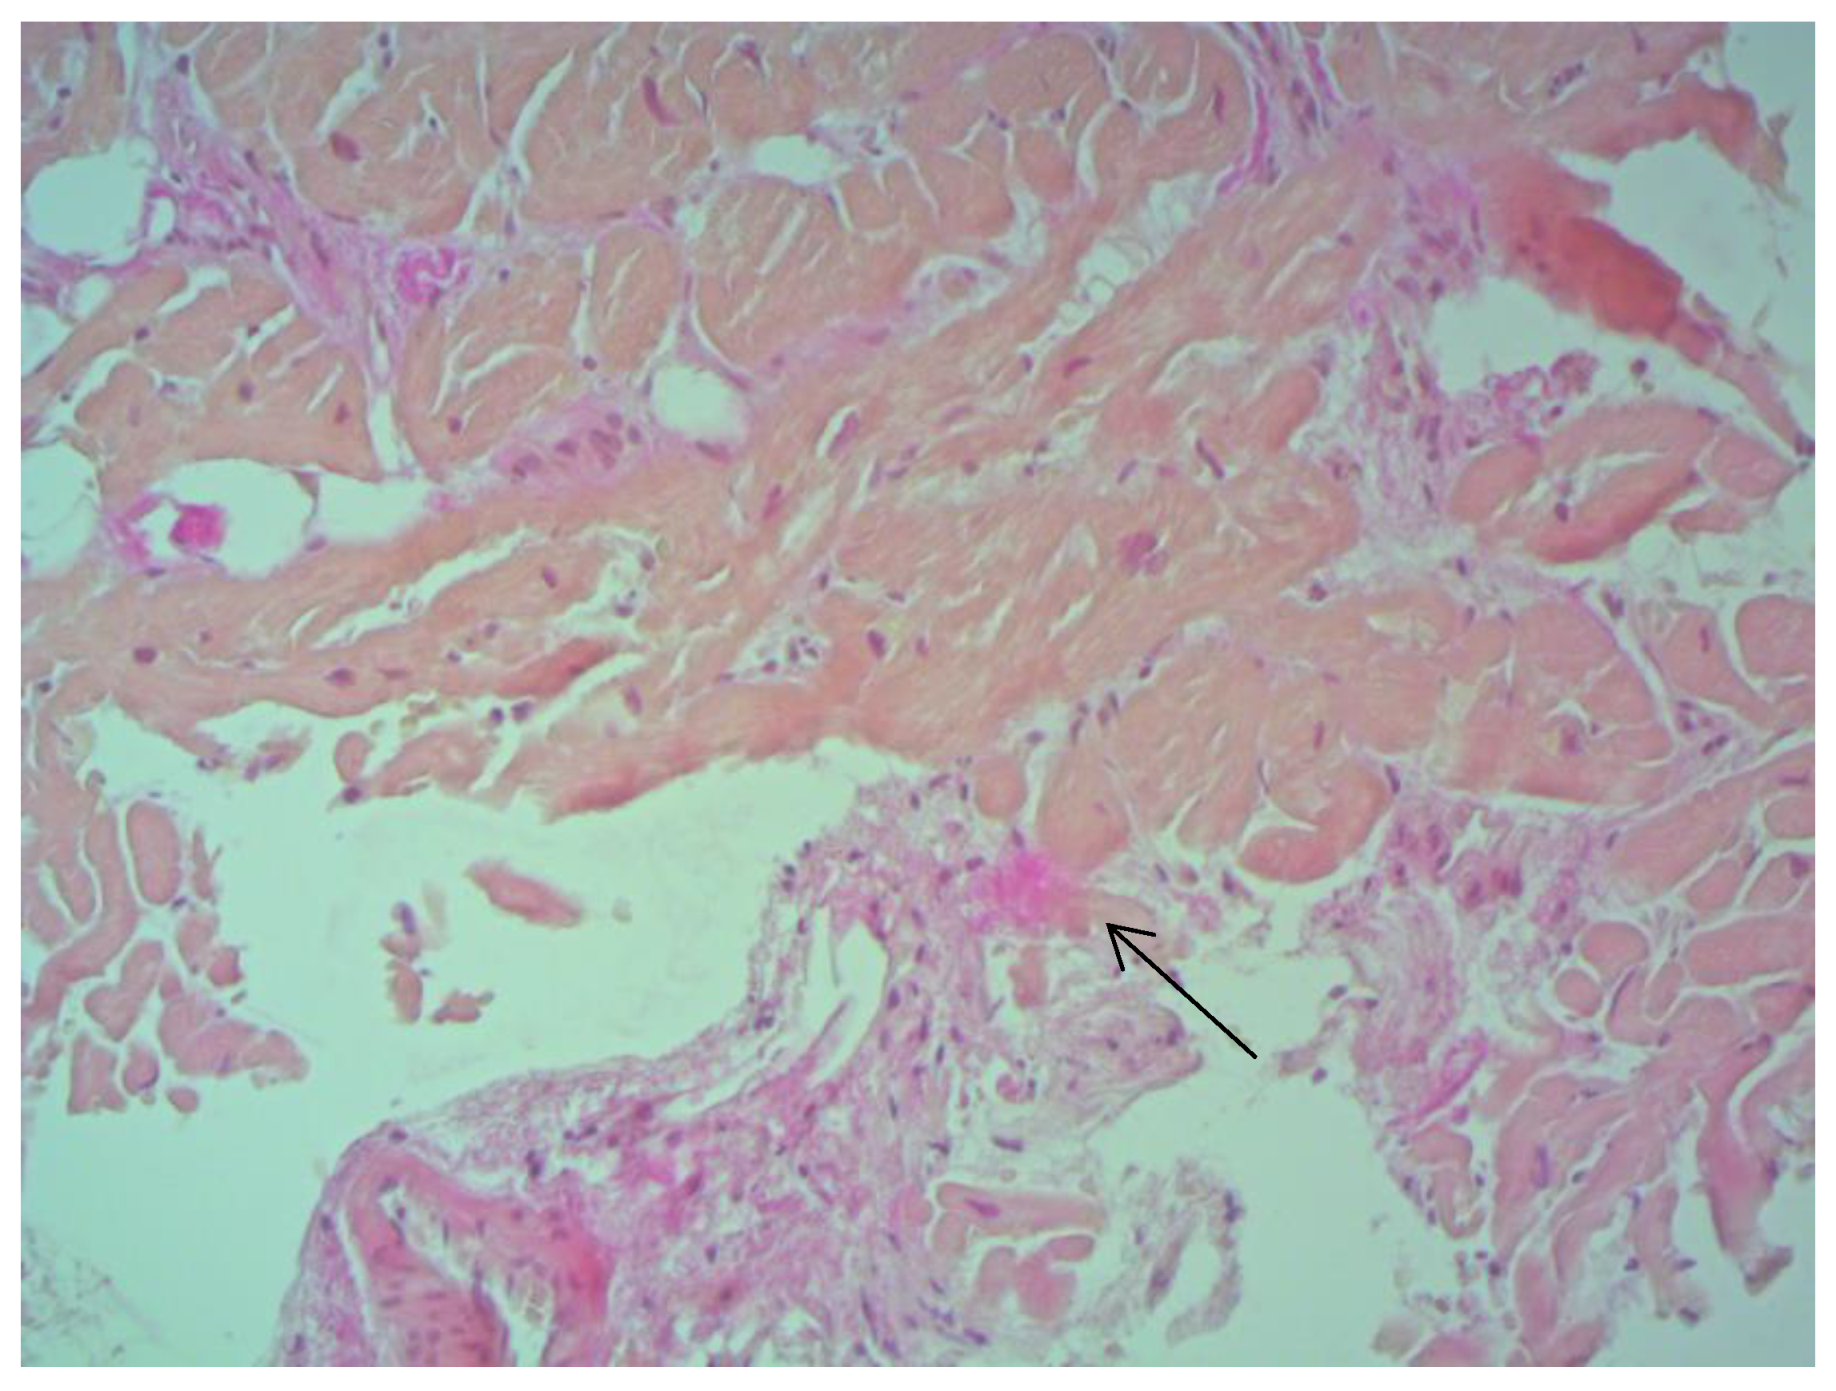

Figure 2. Small focal fibrosis in IVS ×200, staining according to Van Gieson. The arrow indicates the focus of connective tissue proliferation.

According to EMB results, no histological changes in the myocardium of the right ventricle (RV) were found in nine patients (13.4%). Fibrotic changes in the myocardium were detected in 26 cases (38.8%) including in predominantly perivascular fibrosis in 11 patients (42.3%), small focal fibrosis in eight patients (30.8%), and perimuscular fibrosis in seven patients (26.9%) (Figure 1, Figure 2 and Figure 3).